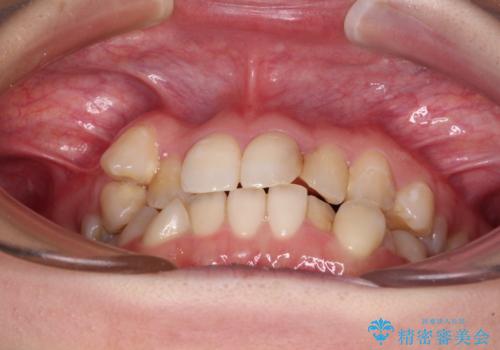

- 上下の八重歯と前歯のデコボコを気にして来院された患者様です。

右上と左下の八重歯が特に著しく、上顎正中が右側にシフトしていました。

デコボコが強いため小臼歯4本を抜歯し、上顎正中を左側に移動させるために補助装置を使用して、ワイヤー装置にて矯正治療を行うこととしました。

八重歯のためずれていた上下の正中をほぼ一致する位置に整えることができました。

重なって汚れの溜まりやすかった部分も改善され、大変満足していただけました。